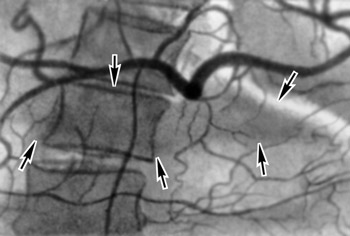

Есть люди, которые любят жару, получая удовольствия от каждого солнечного лучика, обожают загорать на пляже. Но кто-то не выносит жару, и всё лето предпочитает прятаться в тени, осенью таких людей выдаёт молочно-белый цвет кожи. Но и те, и другие рискуют получить солнечный или тепловой удар . Солнечный удар - острое болезненное состояние, возникающее в результате перегрева головы под прямыми солнечными лучами. Вследствие этого сосуды мозга расширяются, получается сильный прилив крови к ...